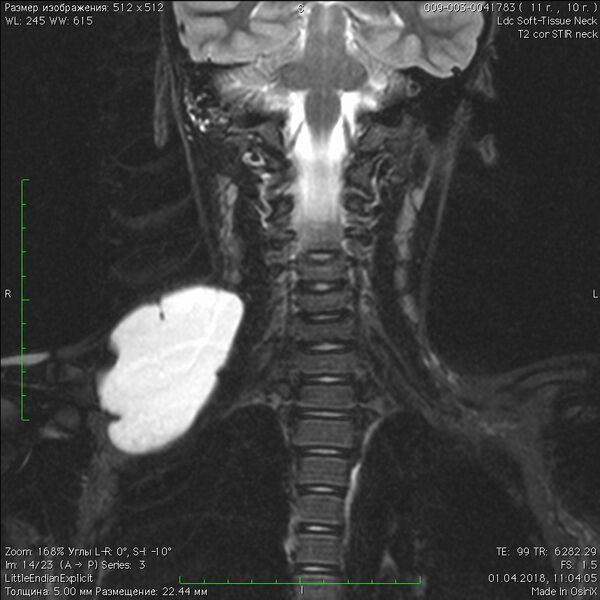

При магнитно-резонансной томографии очаги имеют многодольчатое перегородчатое строение. Они характеризуются изо- или гипоинтенсивным сигналом на Т1-взвешенных изображениях и гиперинтенсивным сигналом на Т2-взвешенных изображениях, а также в режиме подавления сигнала от жира, поскольку эти кистозные образования могут быть различных размеров и часто заполнены жидкостью. Внутри очагов могут наблюдаться уровни жидкости. Чистые ЛМ не накапливают контрастный препарат внутри, так как полностью состоят из полостей, заполненных жидкостью и не сообщающихся с венозной системой. Контрастные препараты усиливают сигнал от периферических стенок и перегородок очага, причём усиление капсул и стенок особенно выражено при макрокистозных формах. Микрокистозные ЛМ не демонстрируют значимого усиления. Также может наблюдаться окружающий отёк (лимфедема)[6].